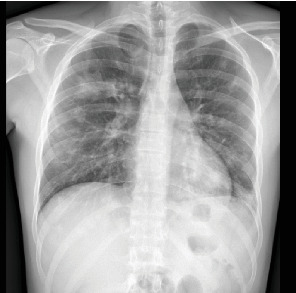

Lemierre综合征(LS)是一种罕见的疾病,估计每年发病率为1-10/1,000,000,定义为口腔和鼻咽感染伴继发性败血症导致脓毒性栓塞和颈内静脉血栓形成的并发症。1936年,在抗生素发明之前,安德烈·勒米尔首次描述了这种综合征。在抗生素出现之前的时代,这是一种常见的疾病,其特征通常是在7-15天内致命,死亡率可高达80%。随着抗生素治疗的发展,LS的发病率迅速下降,如今,它也被称为“被遗忘的疾病”,但死亡率仍然很高(5%),特别是在诊断延迟和治疗不当的情况下。我们提出了一个23岁的病例,他被转介到我们医院,因为咽炎后呼吸困难加剧并伴有高烧,以提高人们对这种严重罕见疾病的认识。如果立即开始适当的治疗,长期的结果通常是好的。肺和血管方面的主要治疗是抗生素治疗,加或不加抗凝和胸管引流。

Lemierre syndrome (LS) is a rare condition with an estimated incidence of 1-10/1,000,000 per year defined as a complication of an oral and nasopharyngeal infection with secondary septicemia leading to septic emboli and internal jugular vein thrombosis. This syndrome was first described by Andre' Lemierre in 1936, before the development of antibiotics. In the preantibiotic era, it was a common condition and it was often characterized by a fatal course within 7-15 days with a mortality rate that could reach up to 80% of cases. After the development of antibiotic therapies, the incidence of LS rapidly declined, and nowadays, it is also known as "the forgotten disease," but the mortality risk remains high (5%) especially in case of diagnostic delay and inappropriate therapies. We presented a case of a 23-year-old who was referred to our hospital for worsening dyspnea associated with high fever following a pharyngitis in order to raise awareness about this severe rare disease. Long-term outcomes are usually good if proper treatment is started with no delay. The mainstays of treatment for the pulmonary and vascular aspects are antibiotic treatment with or without anticoagulation and chest-tube drainage.